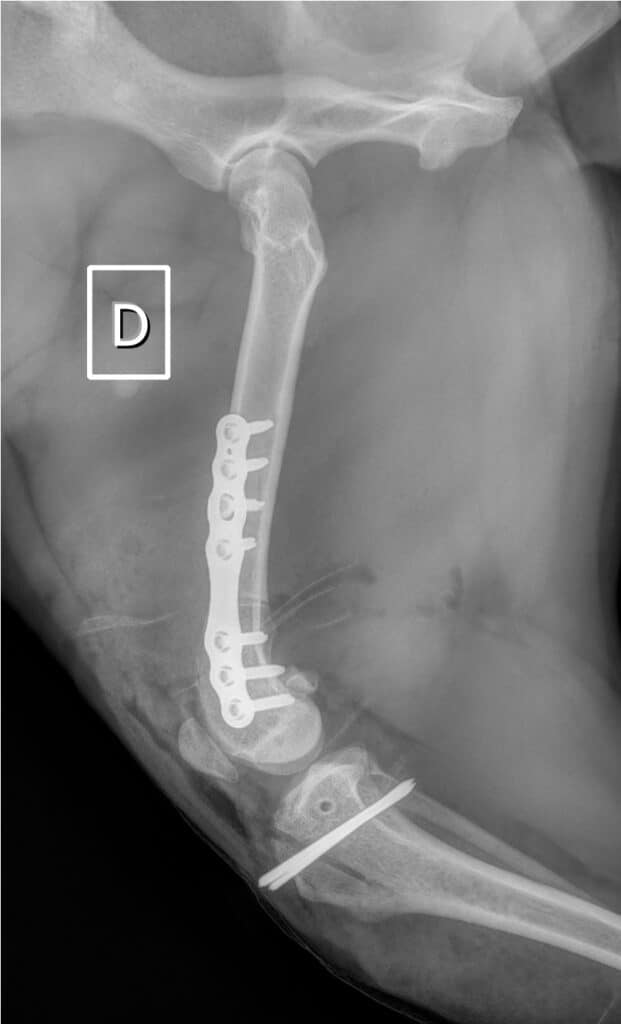

Dans le cas de notre bouledogue qui présentait des déformations osseuses marquées, une ostectomie fémorale latérale dite en « closing wedge » est réalisée en plus des techniques « classiques » présentées ci-dessus. Elle permet de corriger le varus et la torsion, en fixant avec une plaque le fémur proximal et distal, réalignés pour obtenir un angle d’antéversion dans les normes (18°). Les ostéotomies fémorales et tibiales permettent un résultat optimal lorsqu’elles sont indiquées et permettent d’obtenir un très faible taux de récidive de luxation.

Dans le cas de notre bouledogue qui présentait des déformations osseuses marquées, une ostectomie fémorale latérale dite en « closing wedge » est réalisée en plus des techniques « classiques » présentées ci-dessus. Elle permet de corriger le varus et la torsion, en fixant avec une plaque le fémur proximal et distal, réalignés pour permettre un angle d’antéversion dans les normes (18°). Les ostéotomies fémorales et tibiales permettent un résultat optimal lorsqu’elles sont indiquées et permettent d’obtenir un très faible taux de récidive de luxation.